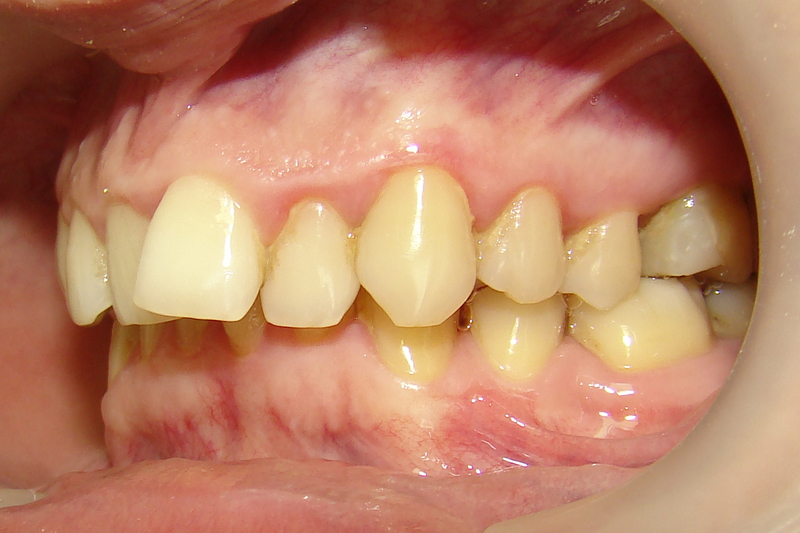

А это уже молодой человек 10 лет. Тоже получилось справиться без удаления. Хоть оно и было показано. Но мальчик очень упорно носил специальные аппаратики и резиночки. Покажу со всех сторон. Этот случай победил в конкурсе на конференции